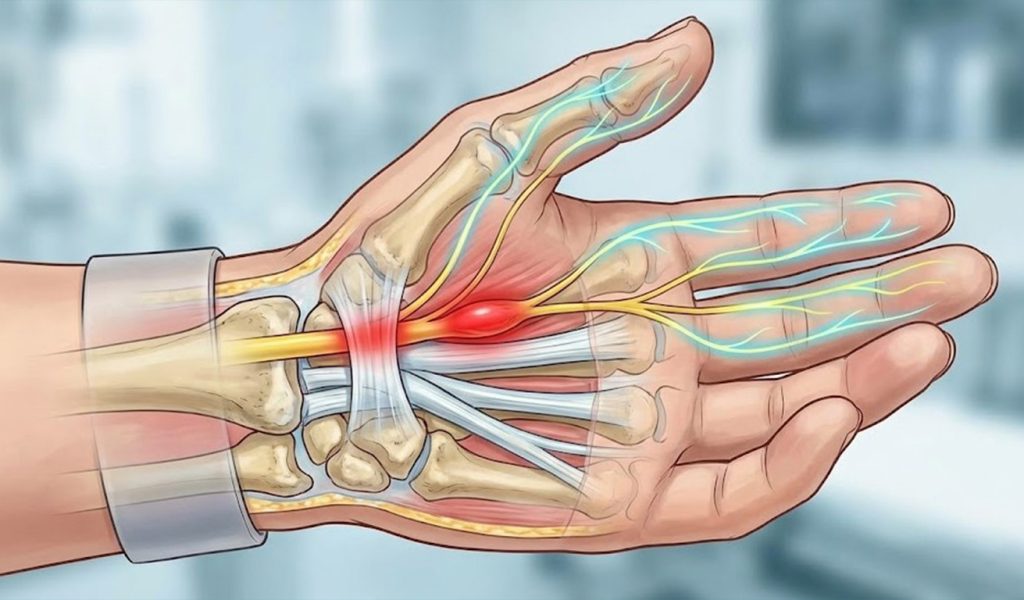

Karpal Tünel Sendromu, el bileğinde bulunan karpal tünel içerisinden geçen median sinirin baskı altında kalmasıyla ortaya çıkan yaygın bir sinir sıkışması hastalığıdır. Özellikle uzun süre bilgisayar kullananlar, el bileğini tekrarlayıcı hareketlerle zorlayanlar ve gece el uyuşması yaşayan kişilerde sık görülür.

Hastalar çoğu zaman şikâyetlerini önemsemez. Oysa karpal tünel sendromu nedir sorusunun cevabı, ilerleyici ve kalıcı hasara yol açabilen ciddi bir ortopedik problemdir.

Karpal tünel sendromu, el bileği kanalında daralma veya sinir üzerinde baskı oluşması sonucu gelişir. Bu durum çeşitli faktörlerle tetiklenebilir.

Bu noktada karpal tünel sendromu nedir sorusu kadar, nedeninin doğru belirlenmesi de tedavinin başarısını doğrudan etkiler.

Karpal Tünel Sendromu Belirtileri Nelerdir?

Karpal Tünel Sendromu genellikle yavaş ilerler ve başlangıçta hafif belirtilerle kendini gösterir.

En sık görülen belirtiler:

- Gece artan el uyuşması

- Başparmak, işaret ve orta parmakta karıncalanma

- El gücünde azalma

- Objeleri tutmakta zorlanma

- Bilekten kola yayılan ağrı

- Bu belirtiler göz ardı edildiğinde sinir hasarı ilerler ve tedavi süreci zorlaşır. Bu nedenle erken tanı, karpal tünel sendromu tedavisi açısından kritik öneme sahiptir.